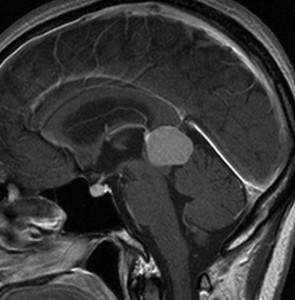

成人女性の松果体細胞腫で充実性腫瘍です。中脳水道が閉塞して軽度の水頭症(頭の中に髄液が溜まる)になってきています。多少凹凸がありますがだいたい楕円形。